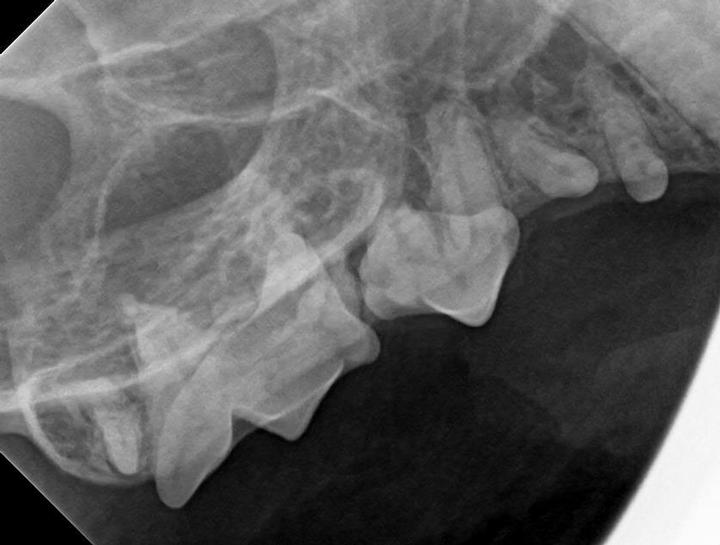

Cat Tooth Xray . Extraoral radiograph (b) showing the same teeth. this article focuses on interpretation of normal anatomic variations as well as congenital and pathologic abnormal findings on dental. This article reviews the indications for, and the importance of, intraoral radiography in dogs and cats. radiographic exposure is controlled by three components:. aim of the article: Most common dental conditions, including periodontal disease. dental radiography forms an integral part of feline practice.

Interpretation of Dental Radiographs in Dogs and Cats, Part 1

Interpretation of Dental Radiographs in Dogs and Cats, Part 2 Normal Cat Tooth Xray radiographic exposure is controlled by three components:. this article focuses on interpretation of normal anatomic variations as well as congenital and pathologic abnormal findings on dental. dental radiography forms an integral part of feline practice. This article reviews the indications for, and the importance of, intraoral radiography in dogs and cats. aim of the article: Most. Cat Tooth Xray.